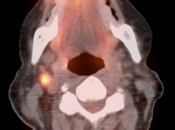

Metastatic Disease:

- Direct invasion of adjacent structures.

- Lymphatic spread to pelvic and retroperitoneal lymph nodes.

- Hematogenous spread, often to lungs, liver, and bone.